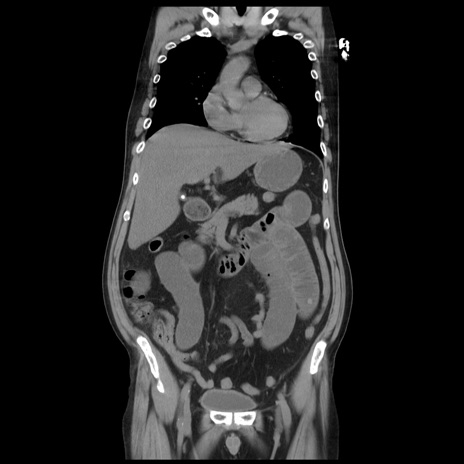

症例20(冠状断像)

【症例】 60歳代男性

【主訴】 腹部膨満、嘔吐

【現病歴】5日前頃より倦怠感を認め食事量減少し4日前の朝嘔吐、食事摂取困難となった。 3日前近医受診し点滴施行され整腸剤などを処方された。 当日他院を受診し、腹部膨満著明、炎症反応の上昇(CRP10.8、WBC11200)あり、紹介受診となる。

【身体所見】 意識JCS1 受け答えがはっきりしないBP 111/57mHg、 P 67bpm、、BT35.2°C、SpO2 97%(RA)、 腹部:膨隆、打診で鼓音あり、全体的に圧痛有り、腸蠕動音(-)、反跳痛ははっきりせず。

【データ】WBC 11400、CRP 14.20